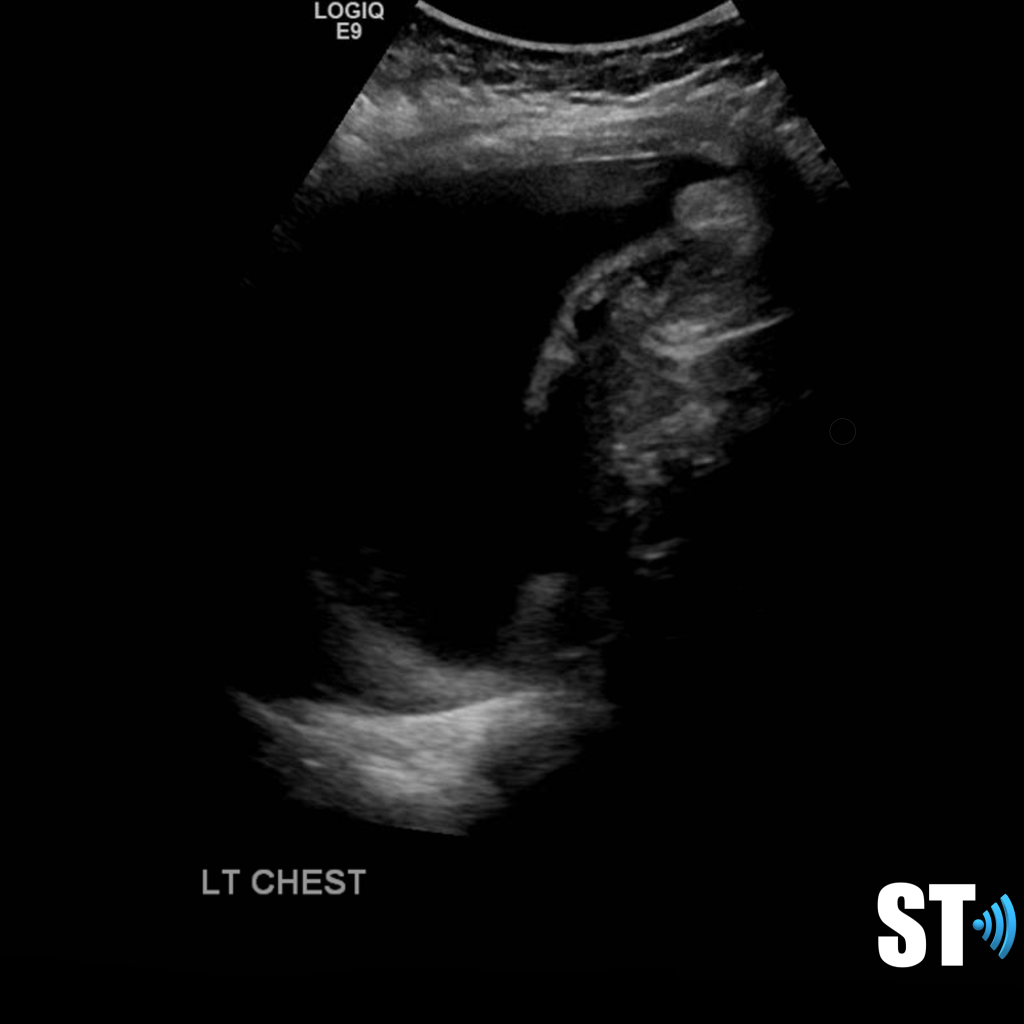

Loculated pleural effusion

complex left pleural effusion